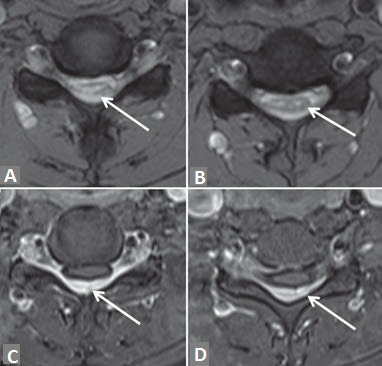

Given the young age of patient and focal spinal cord atrophy, a dynamic evaluation of the cervical spine with flexion and extension was performed. MRI during neck flexion on T2-weighted images [Figure 1b and c] revealed anterior displacement of the posterior dura with epidural flow voids and compression of the spinal cord. Flexion pre and postcontrast T1 MRI in midline sagittal plane [Figure 2a and b] revealed enhancement in posterior epidural space suggestive of enhancement of epidural plexus. Axial postcontrast T1 flexion MRI [Figure 3c and d] demonstrates thinning of the spinal cord, more prominent in right hemicord with posterior epidural enhancement. On extension in postcontrast T1 [Figure 2c], the posterior epidural space and its enhancement disappeared consequent to posterior displacement of posterior dura, also the cord compression was relieved.

Figure 1: T2-weighted sagittal magnetic resonance imaging in neutral position (a) and in neck flexion (b and c) demonstrate anterior displacement of the posterior dura (white arrow in b) with thinning of the spinal and myelomalacia (white arrow in a and c). Epidural fl ow voids posterior to dura also seen (b and c)